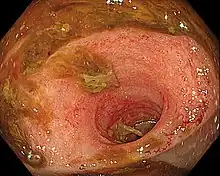

Ileitis caused by capecitabine

Ileitis is an inflammation of the ileum, a portion of the small intestine.[1] Crohn's ileitis is a type of Crohn's disease affecting the ileum. Ileitis is caused by the bacterium Lawsonia intracellularis. Inflammatory bowel disease does not associate with Lawsonia intracellularis infection.